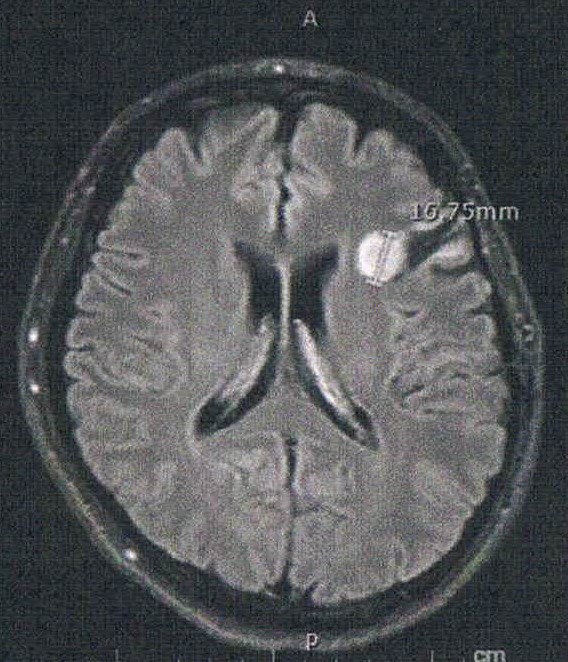

- びまん性星細胞腫グレード2(悪性転化しやすい腫瘍)

- 初めて前後方向に断面を見た気がするが、2年前の画像と比べると上方向に顕著に大きくなっている。

- 造影剤の有無でも見え方が違うのかもしれないが、上下方向は明らかに大きくなっている。玉子で例えると、直径は変わらないが上下が大きくなっている。